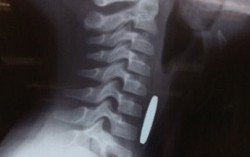

Phòng & chữa bệnh 13:01 13/04/2018Trong lúc đùa nghịch tranh giành đồng xu với em, bé trai Nguyễn Hoàng Quân đã bị đồng xu rơi vào cổ họng. Ngay sau khi tai nạn xảy ra, bé bị nôn ọe và khó thở nên gia đình nhanh chóng đưa đi cấp cứu.

Chính trị - Xã hội 09:41 04/04/2018Đồng xu nằm trong thực quản bé gái 5 tuổi được các bác sĩ nội soi gắp ra thành công. Nếu không gắp kịp thời thì dị vật có thể bị nghẹt lại ở thực quản gây nguy hiểm cho bệnh nhi.